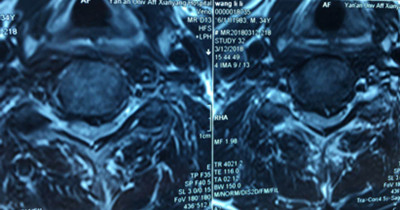

患者王先生,34歲,兩個月來自覺行走時雙下肢無力,伴踩棉花感,休息后癥狀無明顯緩解,雙手指麻木,呈加重趨勢。一月前就診于骨一科。確診為頸椎?。顾栊停?。病變部位位于頸5-6平面。

圖片一: